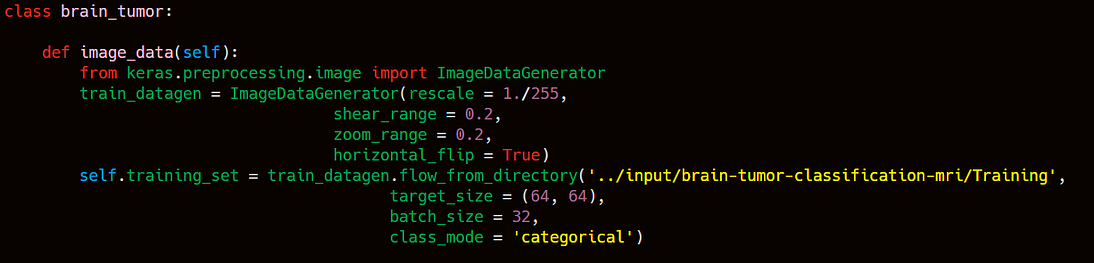

As you can see in the above image that i have created a class named brain_tumor which have a function named image_data. This function will helps us to create a training set of brain MRI images. I have imported ImageDataGenerator from keras.preprocessing. ImageDataGenerator function will helps us to create a image set by following parameteres.

- rescale → it will help to rescale the image by 1./255.

- shear_range → this will helps us to shear the image by 20%.

- zoom_range → this will help to zoom the mage by 20%.

- horizontal_flip= True → Helps to flip the image horizontally. After tha we have to import the images from the directory using flow_from_directory function. Here flow_from_directory have folllowing parameters which will helps us to create a set of training data.

- targe_size= (64,64) → Target(final) image will be of 64 * 64 pixel.

- batch_size= 32 → The default ‘batch_size’ is 32, which means that 32 randomly selected images from across the classes in the dataset will be returned in each batch when training.

- class_mode = ‘binary/categorical’. Here binary means 2 classes whereas categorical means more than two classes. As we having 4 classes so i am taking classmode as categorical. Now the same process we have to do it for testing dataset. The same process has done in the below image to create a testing dataset.